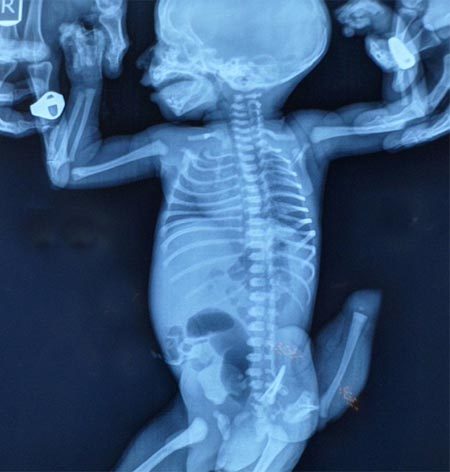

Sự việc hy hữu xảy ra đối với đứa con thứ 4 của cô Jamnibhen Patel, đến từ làng Fatehgarh ở Gujarat, Ấn Độ. Các bác sĩ xác định, chiếc đuôi dị thường của cậu bé sơ sinh thực chất là người anh em song sinh dính liền, phát triển bất đối xứng và chưa hoàn thiện về mặt giải phẫu học.

Bé sơ sinh 5 ngày tuổi rốt cuộc đã trải qua cuộc phẫu thuật kéo dài 4 tiếng đồng hồ để loại bỏ chiếc đuôi nặng 350g, mặc dù việc giữ lại nó có thể đem lại cho em một cuộc sống được tôn sùng ở Ấn Độ.

Tiến sĩ Rohit Joshi, giám đốc bệnh viện tiến hành phẫu thuật cho con cô Patel, giải thích, trường hợp song sinh dính liền bất đối xứng như của cậu bé này rất khác với các ca song sinh dính liền đối xứng, vì chúng không có các kết nối quan trọng ở hệ thống mạch dẫn truyền, ruột hay các xương. Y học ghi nhận hiện tượng song sinh dính liền đối xứng phổ biến hơn ở Ấn Độ và châu Phi.